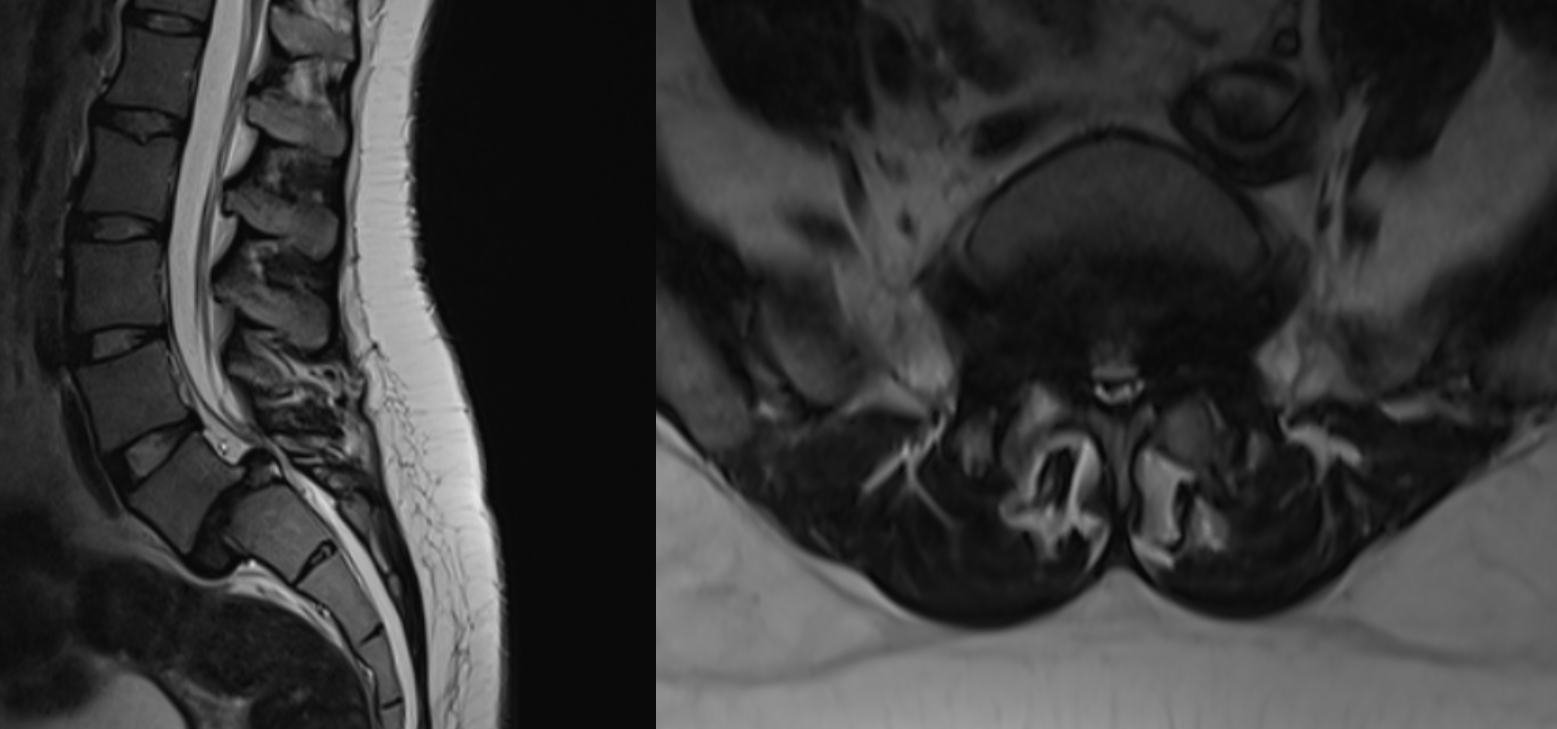

The literature also showed that long-standing cases, as in this patient with a two-year history of symptoms, have guarded prognosis for sphincter recovery. Pain relief, motor improvement, and functional ambulation are achievable after decompression and stabilization with pedicle screw, connecting rod and autologous bone graft (Figure 5).9 Case reports and prospective studies showed that urinary and bowel dysfunction may improve gradually after surgery, but complete recovery is not always possible. So, Surgical decompression and stabilization are standard of care to prevent further deterioration, but chronicity of symptoms must be taken into account when counseling patients regarding outcomes.

Figure 5